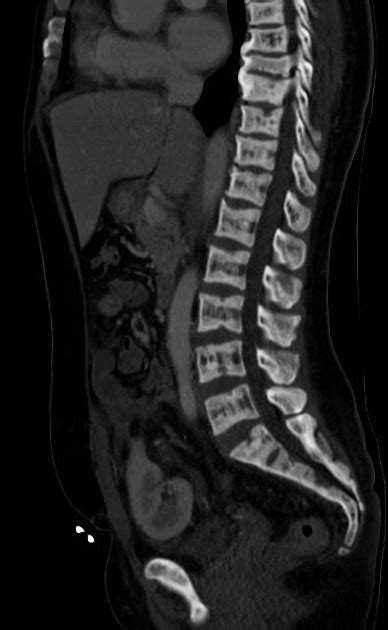

Now, where does a bone scan fit into all this? A bone scan, also known as a bone scintigraphy, is a powerful imaging technique that helps doctors visualize areas of abnormal bone activity. It involves injecting a small amount of radioactive tracer into your bloodstream. This tracer travels throughout your body and collects in areas where there’s increased bone metabolism or repair. Think of it like a highlighter for your bones, pointing out where the action is happening. For renal osteodystrophy, a bone scan can reveal areas of increased bone turnover , which often occurs as the body tries to compensate for the mineral imbalances. It can also help identify fractures that might not be easily visible on regular X-rays, especially stress fractures or subtle breaks. The scan provides a whole-body view , which is super beneficial because bone problems related to kidney disease can affect multiple areas. Doctors can use the information from a bone scan to help diagnose renal osteodystrophy, assess its severity, and monitor how treatment is working. It’s not just about seeing the damage; it’s about understanding the process that’s happening within the bones. The sensitivity of bone scans allows for the detection of metabolic bone disease before significant structural changes are apparent on plain radiography. This early detection is crucial for initiating timely interventions that can help preserve bone integrity and reduce the risk of debilitating fractures. The distribution and intensity of tracer uptake can offer clues about the specific type of bone disease present, guiding further diagnostic and therapeutic decisions. For instance, a generalized increase in uptake might suggest a widespread metabolic issue, while focal uptake could indicate a fracture or a more localized bone lesion. The dynamic nature of bone remodeling in renal osteodystrophy means that scans can be particularly informative, capturing the body’s ongoing attempts to repair and remodel compromised bone tissue. Therefore, the bone scan is not merely a static image but a functional assessment of bone health in the context of kidney disease. The detailed information it provides is invaluable for clinicians managing patients with CKD, helping them to navigate the complexities of bone health and make informed decisions about patient care. It’s a truly remarkable tool in the diagnostic arsenal for this condition.

So, how does this magic happen? The process is pretty straightforward, guys. You’ll have a small amount of a radioactive substance, called a radiotracer , injected into a vein, usually in your arm. Don’t worry, the amount is tiny and considered safe. Then, you’ll typically need to wait a few hours – sometimes up to 4 hours – for the tracer to circulate through your body and settle into your bones. During this waiting period, you can usually go about your normal activities, though you might be asked to drink plenty of water to help the tracer distribute evenly and clear from your urinary tract. Once the waiting period is over, you’ll lie down on a scanning table, and a special camera called a gamma camera will slowly move over your body. This camera detects the radiation emitted by the tracer. Areas where there’s more tracer uptake will appear brighter on the scan images, indicating increased bone activity. The entire scanning process usually takes about 30 to 60 minutes. It’s a non-invasive procedure, meaning no surgery or incisions are involved, making it a comfortable experience for most patients. The key principle behind the bone scan is that areas of high bone turnover, such as those seen in active bone disease, inflammation, or healing fractures, will take up more of the radiotracer compared to normal bone. This heightened metabolic activity signals that something is happening in those specific bone regions. In the context of renal osteodystrophy, this could be the body’s attempt to remodel weakened bone or areas where micro-fractures have occurred due to bone fragility. The ability to visualize the entire skeleton in a single scan is a major advantage, allowing for a comprehensive assessment of bone health throughout the body, which is particularly useful given that renal osteodystrophy often affects multiple bones. The clarity and detail provided by modern gamma cameras, often combined with SPECT (Single-Photon Emission Computed Tomography) for enhanced 3D imaging, offer clinicians a detailed roadmap of bone abnormalities. This allows for a more precise diagnosis and targeted treatment planning, ultimately aiming to improve outcomes for patients suffering from this challenging condition. It’s a sophisticated yet accessible method to peer inside the skeletal system.

When it comes to renal osteodystrophy , a bone scan is incredibly valuable because it can detect subtle changes that might be missed by other imaging methods. It’s particularly good at highlighting increased bone turnover , which is a hallmark of this condition. This increased turnover is the body’s way of trying to repair or remodel weakened bones that are struggling due to the imbalances in calcium, phosphorus, and vitamin D caused by kidney failure. The scan can pinpoint specific areas where this process is most active. Another crucial thing a bone scan can detect is fractures . In patients with renal osteodystrophy, bones become fragile and brittle, making them susceptible to fractures, even from minor stress or trauma. These fractures might be small or located in areas that are hard to see on standard X-rays. A bone scan will light up these fracture sites because the bone around a fracture is undergoing rapid repair and remodeling, attracting more of the radiotracer. Beyond just fractures and general turnover, the scan can also help identify bone pain origins. If you’re experiencing bone pain, the scan can show if it’s related to areas of increased bone activity, helping doctors understand the cause of your discomfort. It can even help differentiate between different types of bone abnormalities associated with kidney disease, such as osteomalacia or osteitis fibrosa cystica, by the pattern of tracer uptake. While it doesn’t provide the detailed soft tissue or internal bone structure information that an MRI or CT scan does, its strength lies in its sensitivity to metabolic changes and its ability to visualize the entire skeleton. This makes it an indispensable tool for assessing the systemic impact of renal osteodystrophy on bone health. The sensitivity of bone scintigraphy in detecting increased osteoblastic activity means it can often identify abnormalities at an earlier stage than conventional radiography, allowing for earlier intervention and potentially mitigating the progression of bone disease. This early detection is crucial for preventing severe complications like debilitating fractures and chronic pain, thereby improving the overall quality of life for individuals living with kidney disease. The comprehensive skeletal survey provided by a bone scan is essential for understanding the full extent of skeletal involvement, aiding in the development of personalized treatment plans. It’s truly a window into the dynamic state of your bones.